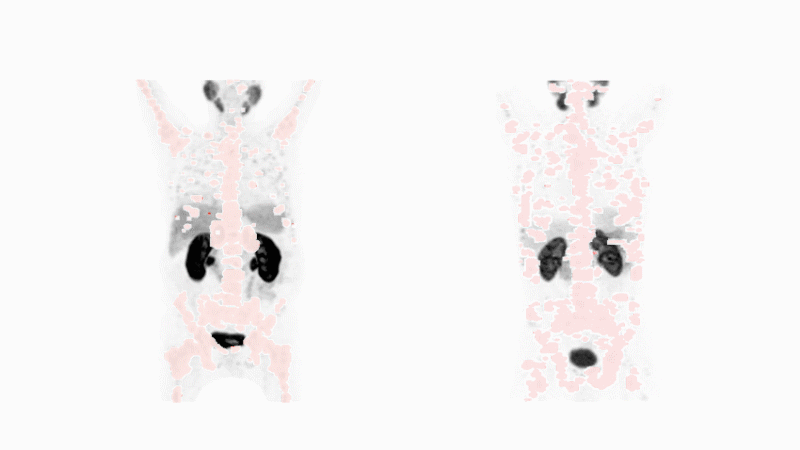

Nuklearmedizin hat auch eine diagnostische Komponente. Sie verwendet das gleiche tumorspezifische Molekül wie in der Krebstherapie, liefert aber radioaktive Atome, die das Potenzial haben, Krebs zu identifizieren und zu lokalisieren. Diese Atome senden Gammastrahlen aus, die von speziellen Scannern erkannt werden. Findet das Medikament den gesuchten Krebs, wird er enthüllt - egal wo er sich im Körper versteckt. Dies gilt selbst für winzige Stellen, die ein Chirurg nicht herausschneiden könnte. Bild von Michael Hofman, mit freundlicher Genehmigung von Journal of Nuclear Medicine. Animation von Fidelis Onwubueke

Die Nuklearmedizin hat auch eine diagnostische Komponente. Sie verwendet das gleiche tumorspezifische Molekül wie das Therapeutikum, um Krebs zu identifizieren und zu lokalisieren.

Diese Atome geben eine Form von Energie ab, die nur geringen Schaden anrichtet. Sie ähnelt einer Lichtwelle, die ausserhalb des Körpers von bildgebenden Scannern erkannt werden kann. Nun können Ärzte den Krebs sehen - unabhängig davon, wo er sich im Körper ausgebreitet hat.

Nur wenn die molekularen Puzzleteile übereinstimmen, kann die Diagnose den Krebs eines Patienten aufdecken. Wenn dies der Fall ist, ist eine gezielte Radioliganden-Therapie mit dem gleichen tumorspezifischen Molekül eine angemessene Behandlungsoption.

Dieser Ansatz der Enttarnung und Behandlung ermöglicht es Ärzten, das passende Medikament für die spezifische Krebsform des Patienten auszuwählen. Darüber hinaus können künftige Scans den Ärzten dabei helfen, festzustellen, ob das Medikament anschlägt und beim Behandlungsfortschritt hilft.